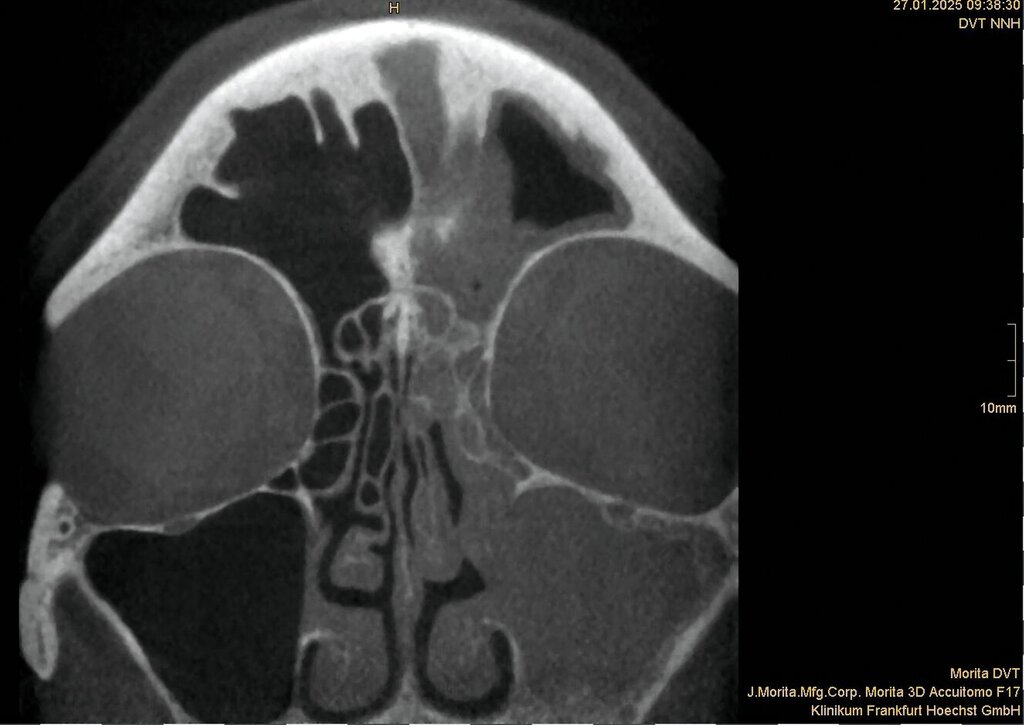

Zwischen März und Oktober 2022 erfolgten dort eine Wurzelkanalbehandlung und später eine Revision an Zahn 26 sowie eine Trepanation von Zahn 27 mit Abfluss von putridem Sekret. Trotz dieser Maßnahmen blieben die Beschwerden bestehen. Ein DVT im Mai 2023 zeigte eine zystische Läsion in regio 27 mit Verdacht auf Kieferhöhlenperforation und bereits vollständiger Verschattung der linken Kieferhöhle (Abbildung 2). Zahn 27 wurde daraufhin extrahiert.

Ein im Februar 2024 durch die HNO veranlasstes DVT bestätigte erneut eine einseitige Pansinusitis (Abbildung 3), ohne den dentalen Bezug zu erfassen. Daraufhin wurde eine chirurgische Sanierung der Nasennebenhöhlen geplant, die jedoch aus Kapazitätsgründen des Krankenhauses nicht durchgeführt wurde. Im Januar 2025 kam es schließlich zu einer akuten Verschlechterung mit starken Schmerzen.